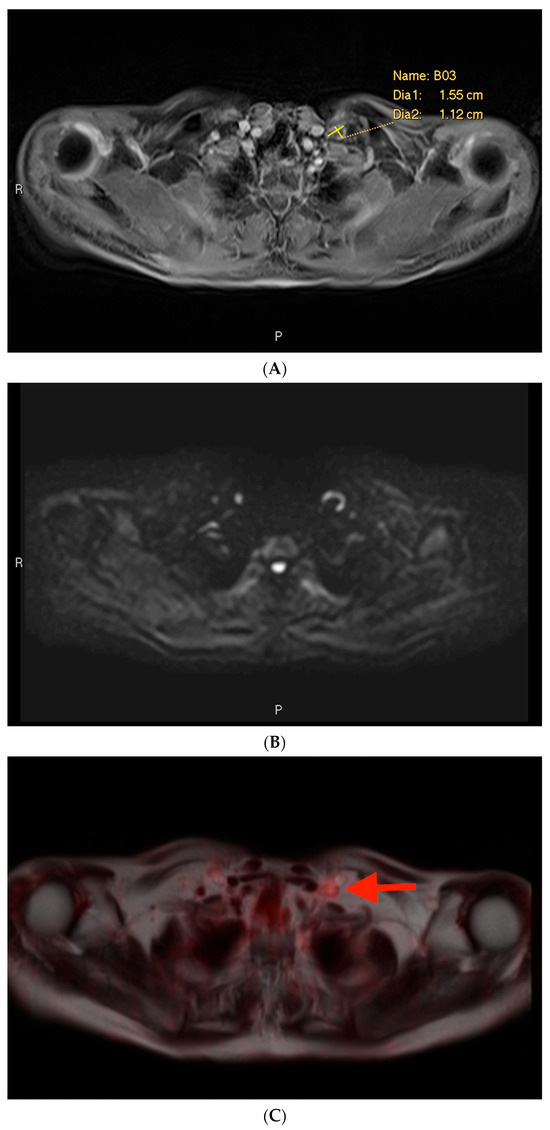

3.2. Example 2—Mischaracterization of Lymph Node Metastasis

Among the cases included in this analysis, there was only one example of a characterization issue, defined as an instance where a lymph node was suspicious on MRI on the basis of size but was not prospectively included in the report (Figure 4). This case involved a lymph node metastasis. The PSMA PET showed a PSMA-avid node in the left supraclavicular region (Figure 4C). The lymph node measured > 1.0 cm in short axis (Figure 4A). However, it also exhibited a benign morphology with an oval shape and a fatty hilum.

Post-contrast fat-saturated gradient T1-weighted image (A), diffusion-weighted imaging with b = 900 s/mm2 (DWI) (B), and fused PET/single-shot T2-weighted imaging (C) through the pelvis. In Figure 3A, the lesion is marked with measurement calipers. In Figure 3B,C, the lesion is denoted with a red arrow. Yellow arrows indicate the ureters, which show physiologic PSMA PET uptake.